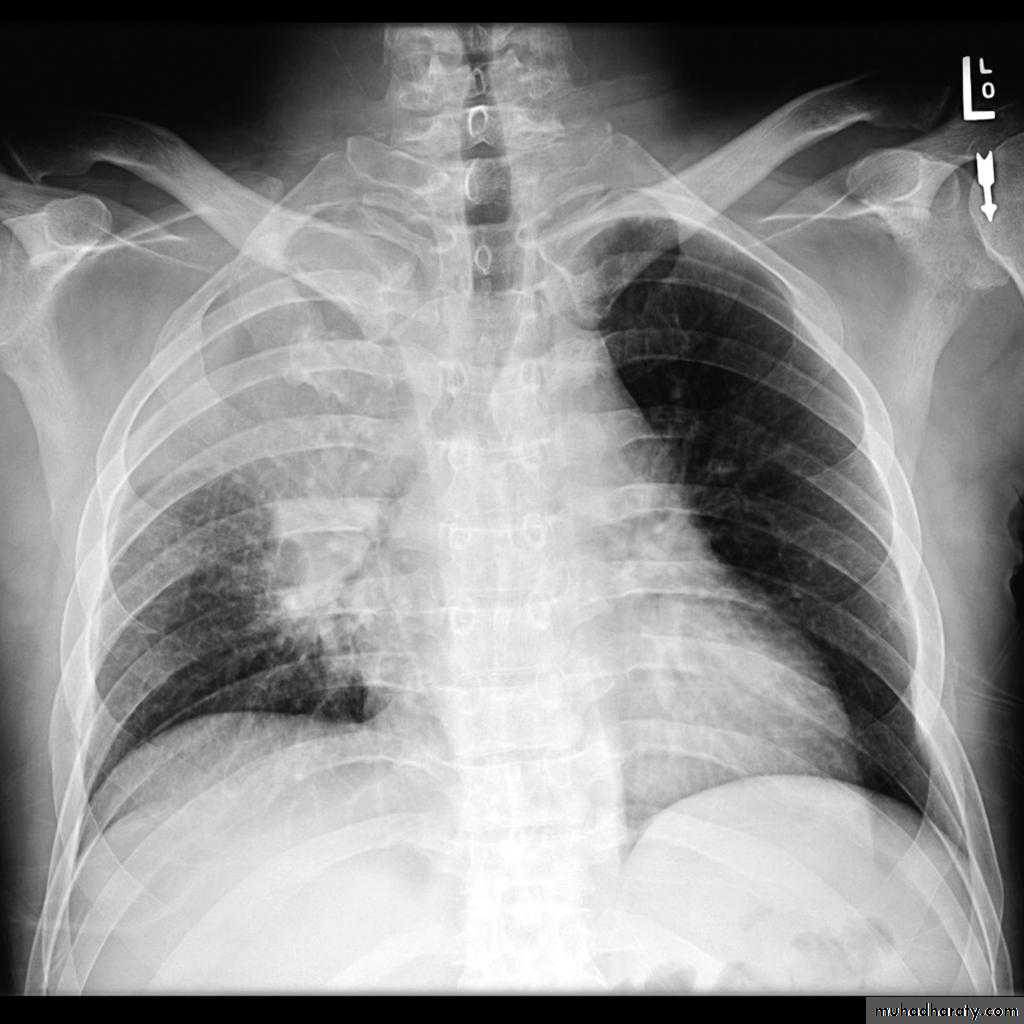

Left upper lobe collapse has distinctive features but can be challenging to identify on chest radiographs by the uninitiated.

Radiographic features

The left upper lobe collapses anteriorly becoming a thin sheet of tissue apposed to the anterior chest wall, and appears as a hazy or veiling opacity extending out from the hilum and fading out inferiorly . It thus reverses the normal slight increase in radiographic density seen as you move down the lung (due to increased thickness of the chest soft tissues).

Parts of the normal cardiomediastinal contour may also be obliterated where the left upper lobe, particularly the lingula abut the left heart border. The anterior parts of the aortic arch are also often obliterated from view.

In some cases the hyperexpanded superior segment of the left lower lobe insinuates itself between the left upper lobe and the superior mediastinum, sharply silhouetting the aortic arch and resulting in a lucency medially. This is known as the luftsichel sign.

The left hilum is also drawn upwards, resulting in an almost horizontal course of the left main bronchus and vertical course of the left lower lobe bronchus.

Non-specific signs indicating left sided atelectasis will also be present, including:

elevation of the hemidiaphragm

'peaked' or 'tented' hemidiaphragm: juxtaphrenic peak sign

crowding of the left sided ribs

shift of the mediastinum to the left

On lateral projections the left lower lobe is hyperexpanded and the oblique fissure displaced anteriorly. There is associated increase in the retrosternal opacity.